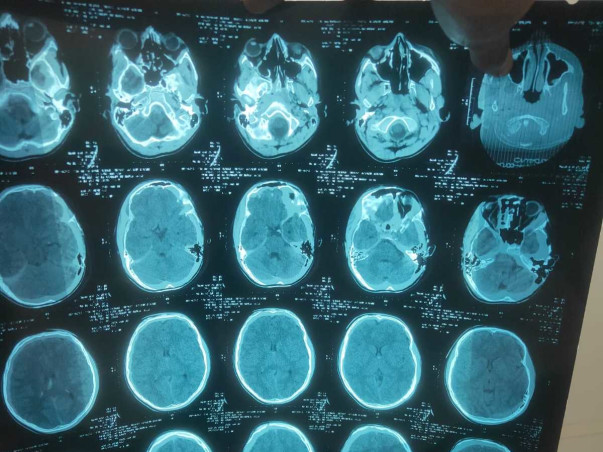

My name is Ashok Kumar and I am here to raise funds for my relative Dipu Kumar who is 13 years old. Dipu Kumar lives in Hazaribag, Jharkhand with his parents. Dipu Kumar is suffering from a Brain injury for a few months.

he is currently admitted and receiving ICU Care in Orchid Hospital, Ranchi, Jharkhand. Until now, we've spent about Rs. 10,00,000.